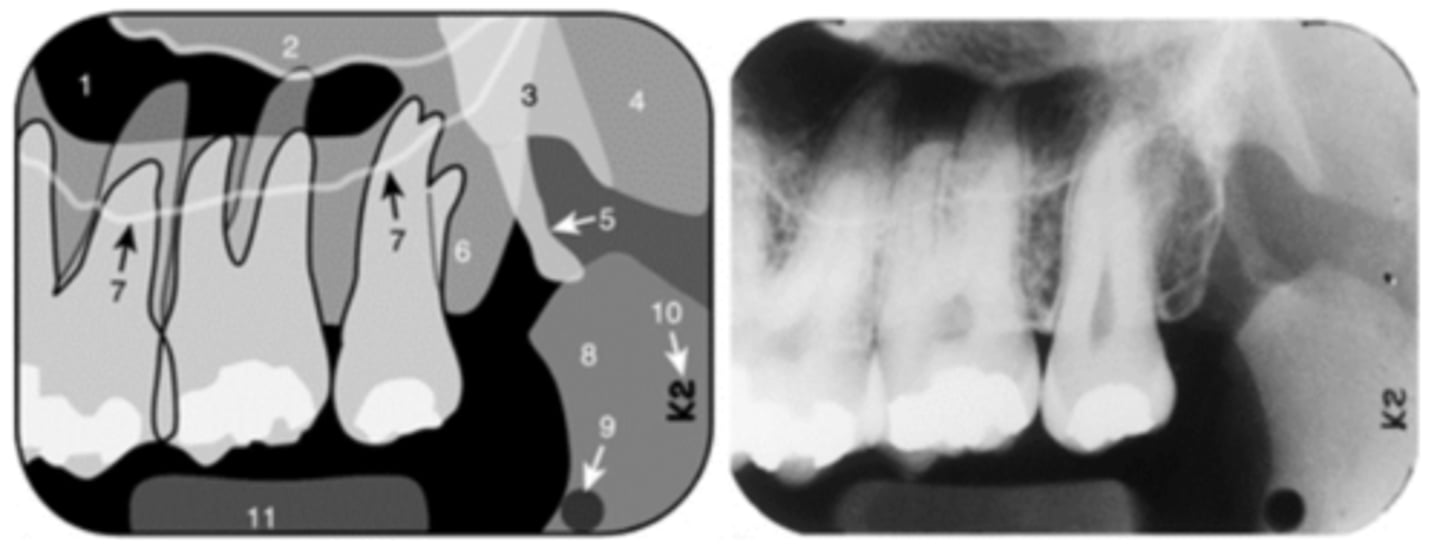

Nasopalatine (incisive) foramen

Identify the round, ovoid radiolucent structure indicated by the black arrows.

<p>Identify the round, ovoid radiolucent structure indicated by the black arrows.</p>

Nasopalatine canal

Identify the straight, radiopaque lines indicated by the white arrows.

<p>Identify the straight, radiopaque lines indicated by the white arrows.</p>

Nasal cavity

In which radiolucent space does the #6 lie?

<p>In which radiolucent space does the #6 lie?</p>

Floor of maxillary sinus

Name the curved, radiopaque line that superimposes the roots of the teeth indicated by #7.

<p>Name the curved, radiopaque line that superimposes the roots of the teeth indicated by #7.</p>

Floor of the maxillary sinus

Name the line indicated by arrows labeled #2.

<p>Name the line indicated by arrows labeled #2.</p>

Hamulus

Name the elongated radiopacity indicated by #5.

<p>Name the elongated radiopacity indicated by #5.</p>

Lateral pterygoid plate

Name the large radiopacity with a rounded inferior margin indicated by #4.

<p>Name the large radiopacity with a rounded inferior margin indicated by #4.</p>

Zygoma

Name the horizontal radiopaque line labeled #2.

<p>Name the horizontal radiopaque line labeled #2.</p>

Name the curved line scalloping between tooth roots labeled #3.

<p>Name the curved line scalloping between tooth roots labeled #3.</p>

Coronoid process

Name the curved, conical structure outlined in the bottom left corner of the image.

<p>Name the curved, conical structure outlined in the bottom left corner of the image.</p>

Lingual foramen

Name the small, radiolucent dot indicated by #4.

<p>Name the small, radiolucent dot indicated by #4.</p>

Lip line

Name the curved radiopacity, the superior border of which is labeled #7.

<p>Name the curved radiopacity, the superior border of which is labeled #7.</p>

Zygomatic process of the maxilla

Name the curved, radiopaque structure indicated by the arrows.

<p>Name the curved, radiopaque structure indicated by the arrows.</p>

Sinus septum

Name the straight (slightly curved), radiopaque structure indicated by the arrows.

<p>Name the straight (slightly curved), radiopaque structure indicated by the arrows.</p>

Superior foramina of the nasopalatine duct

Name the two round radiolucencies indicated.

<p>Name the two round radiolucencies indicated.</p>